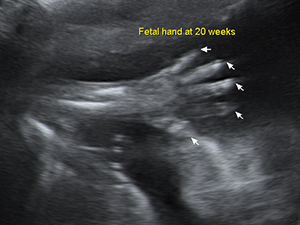

Limps